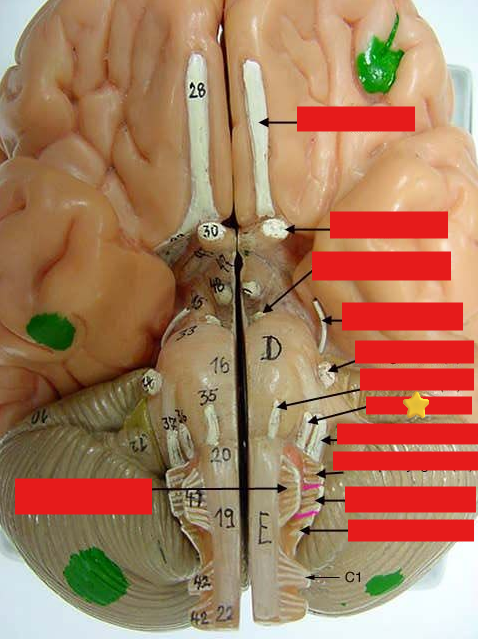

cranial nerves

12 Terms

1

olfactory

2

optic

3

oculomotor

4

trochlear

5

trigeminal

6

abucens

New cards

7

facial

8

vestibulocochlear

New cards

9

glossopharyngeal

New cards

10

vagus

New cards

11

accessory

New cards

12

hypoglossal

New cards